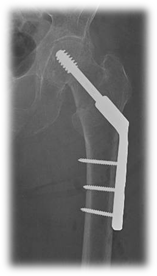

Dentro de estas fracturas, la fractura basicervical (FBC) (Figura 1) presenta un patrón especial. Existe diferencia entre el diámetro del hueso cortical de los fragmentos proximal y distal, lo que la convierte en una fractura inherentemente inestable, tanto en la dirección axial como rotacional, lo que puede conducir al fracaso del implante.

Figura 1 A y B- Fractura de cadera basicervical

Figura 1 A y B